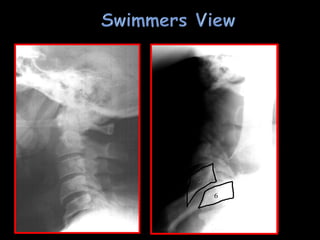

 Lateral C-spinein trauma room › Must include down to C7-T1 › Swimmer’s view or pull-down if necessary › Single most important radiographic examination  C-spine series › AP, Open mouth (dens)  T-L-S spine films as indicated (one spine fracture mandates full spine radiographic evaluation) › T-L junction: 50% of injuries occur at T11-L1